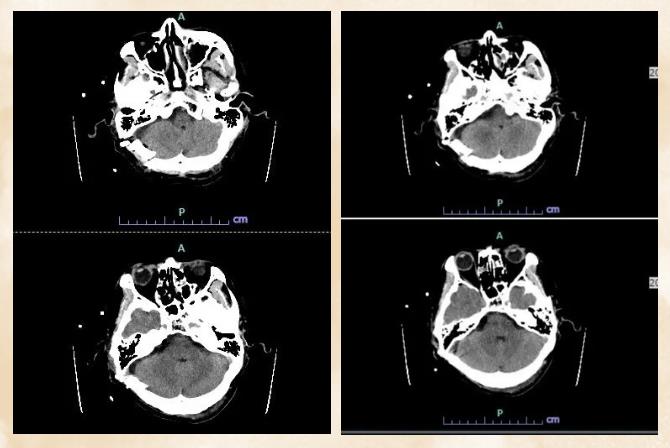

在术前筹备阶段,青海红十字医院神经外科组织本院影像科、麻醉科核心骨干,与济医附院王海涛教授团队通过远程医疗平台开展多轮深度会诊。该院医师详细汇报患者病情、影像资料及初步诊疗思路,结合高原患者生理特点提出诊疗疑问;济医附院专家团队结合丰富临床经验,对手术入路选择、血管神经粘连处理策略及术后并发症防控方案等给出全面指导,最终双方达成共识,确定采用经乙状窦后入路手术方案。

术中探查发现,肿瘤呈珍珠样外观,与脑干腹侧面、小脑前下动脉及多组颅神经粘连异常紧密,剥离空间极度狭小。面对这一突发状况,青海红十字医院手术团队沉着冷静,严格遵循术前既定方案,在顾更诗医师的指导下,运用娴熟的显微外科技术,采取瘤内分块减压、锐性精细剥离相结合的策略,在神经与血管交织的“丛林”中谨慎操作。每一次剥离、每一次止血,都凝聚着两地医者的专业与默契,双方实时交流解剖判断、共同优化手术动作,始终将重要神经血管的保护放在首位。经过数小时的紧张奋战,肿瘤被次全切除(为保护紧密粘连的神经,仅残留极少非功能区囊壁),所有重要神经血管结构完好无损,手术取得圆满成功。